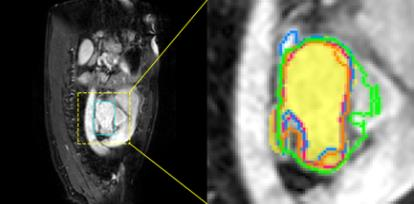

Accurate magnetic resonance imaging (MRI) segmentation is crucial for clinical decision-making, but remains labor-intensive when performed manually. Convolutional neural network (CNN)-based methods can be accurate and efficient, but often generalize poorly to MRI's variable contrast, intensity inhomogeneity, and protocols. Although the transformer-based Segment Anything Model (SAM) has demonstrated remarkable generalizability in natural images, existing adaptations often treat MRI as another imaging modality, overlooking these modality-specific challenges. We present SAMRI, an MRI-specialized SAM trained and validated on 1.1 million labeled MR slices spanning whole-body organs and pathologies. We demonstrate that SAM can be effectively adapted to MRI by simply fine-tuning its mask decoder using a two-stage strategy, reducing training time by 94% and trainable parameters by 96% versus full-model retraining. Across diverse MRI segmentation tasks, SAMRI achieves a mean Dice of 0.87, delivering state-of-the-art accuracy across anatomical regions and robust generalization on unseen structures, particularly small and clinically important structures.